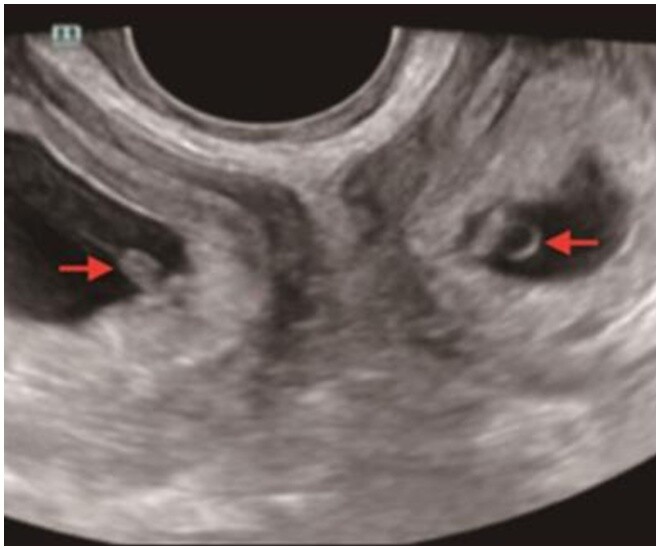

Kết quả thật bất ngờ: suốt thai kỳ, chị tăng cân rất hợp lý, không mắc tiểu đường thai kỳ hay cao huyết áp, những biến chứng thường gặp ở song thai. Các chỉ số của cả mẹ và bé đều ổn định. Đặc biệt, siêu âm cho thấy trong mỗi tử cung của chị đều có một em bé, một trai, một gái, cùng phát triển.

Người mẹ có 2 tử cung, mỗi tử cung đều có một bào thai.